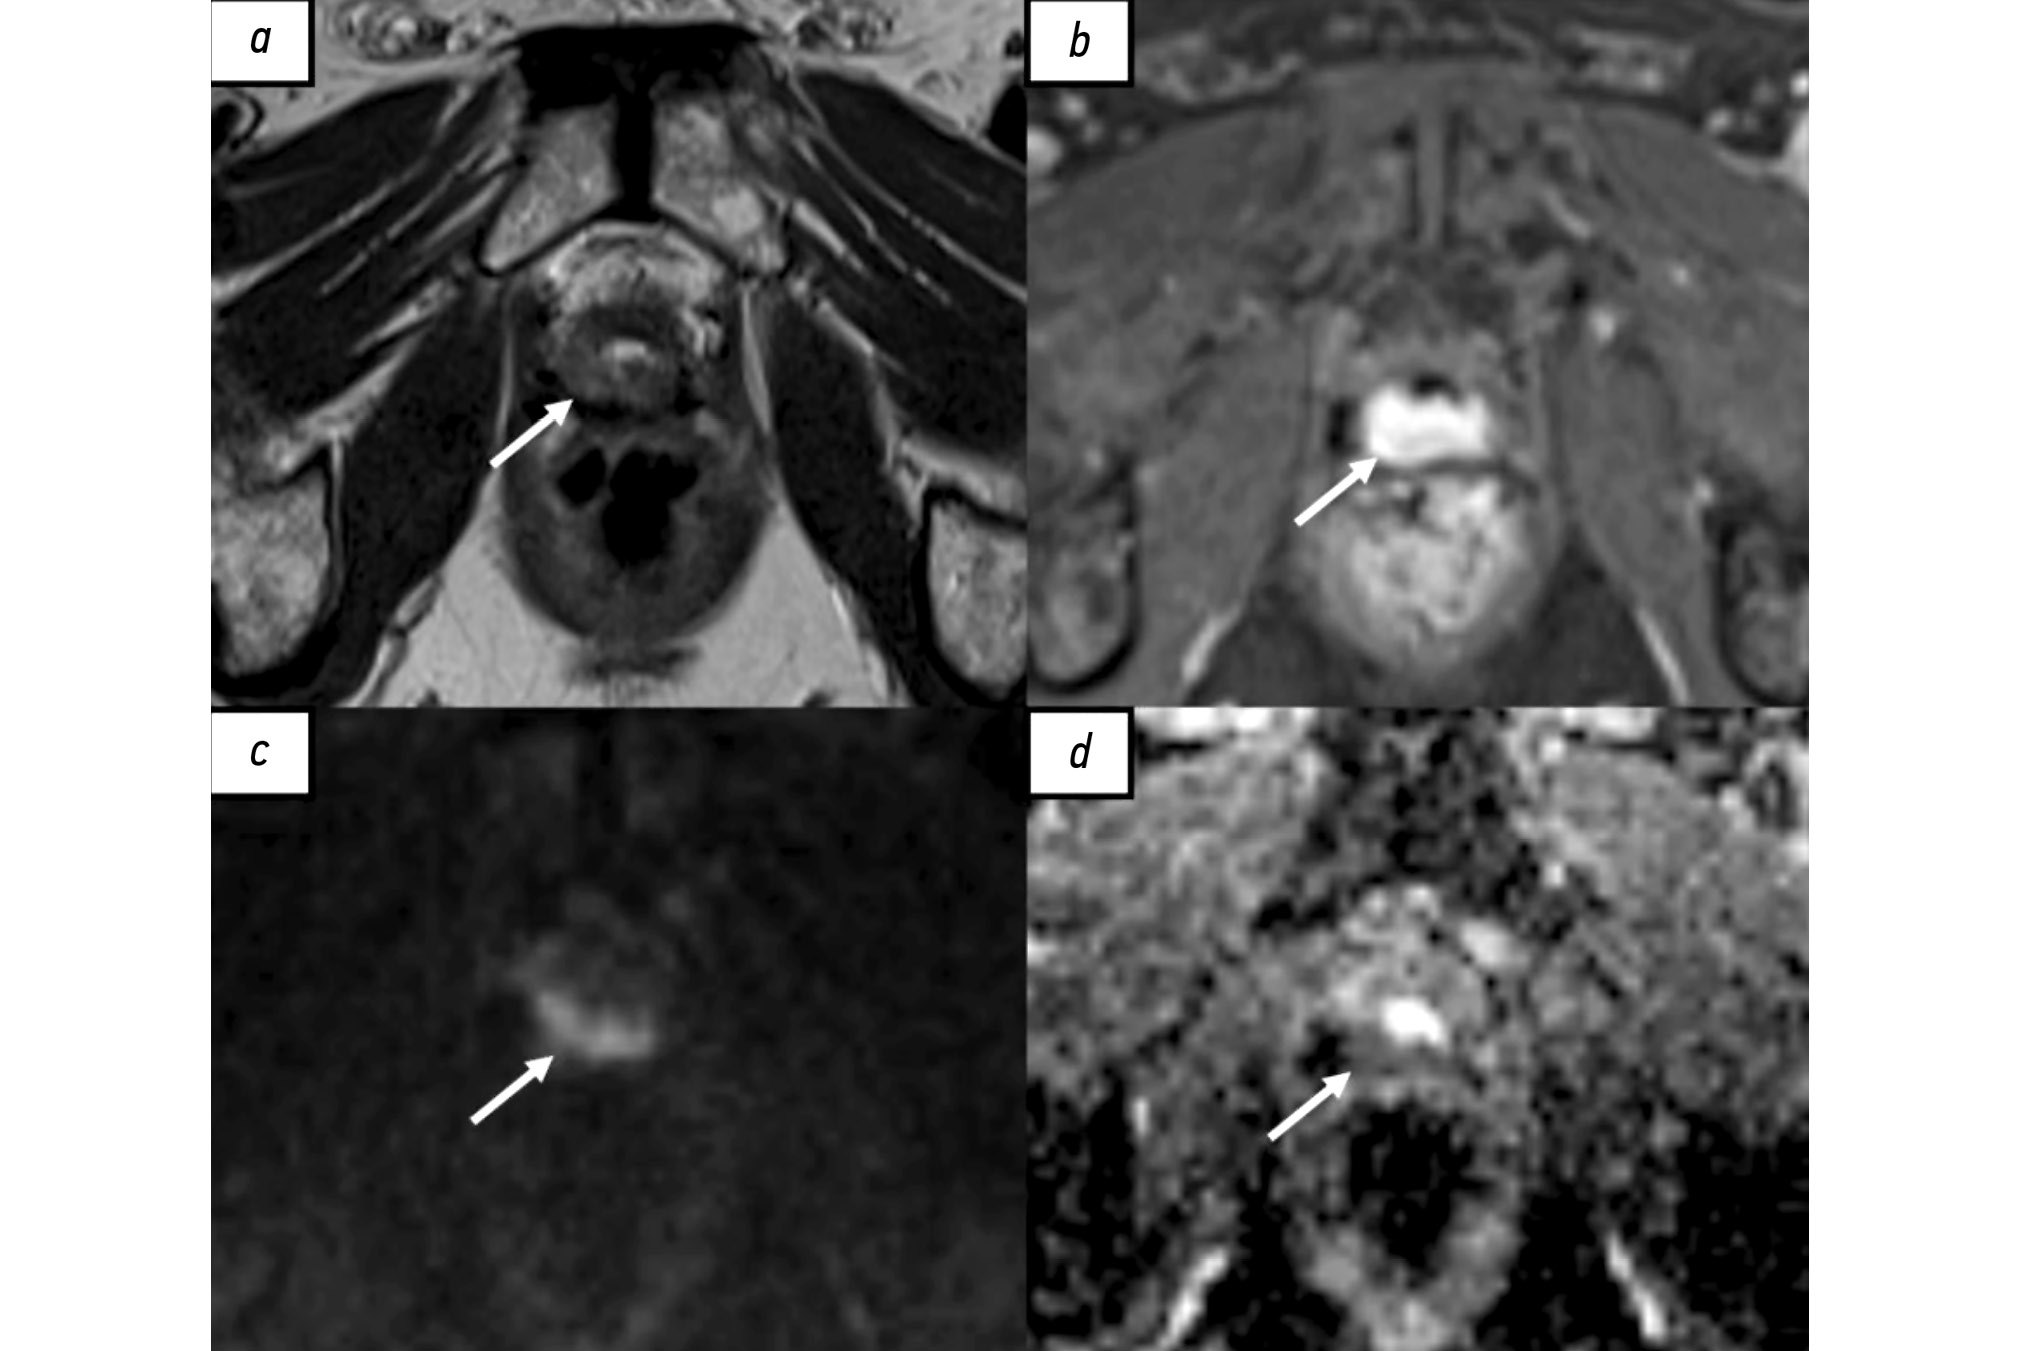

Early detection of orphan diseases, including tuberous sclerosis complex, requires a multidisciplinary approach and the integration of new prenatal diagnostic methods, utilizing ultrasound and magnetic resonance imaging. Accumulated knowledge of the clinical manifestations of tuberous sclerosis complex and advancements in diagnostic techniques enable the identification of this condition. Magnetic resonance imaging allows for high-quality anatomical and functional imaging of the brain in various planes, improving the sensitivity and diagnostic value of the method for early (prenatal) detection of cerebral manifestations of tuberous sclerosis complex. Additionally, magnetic resonance imaging detects mediastinal masses. This highlights the need for a comprehensive approach in diagnosing tuberous sclerosis complex, with magnetic resonance imaging as the primary method for assessing the fetus’s cardiovascular and central nervous systems.

This article presents a clinical case of tuberous sclerosis complex determined by intrauterine diagnosis followed by postnatal examination of the newborn and genetic confirmation of the diagnosis. This case report demonstrates the diagnostic value of magnetic resonance imaging in the prenatal diagnosis of tuberous sclerosis complex.